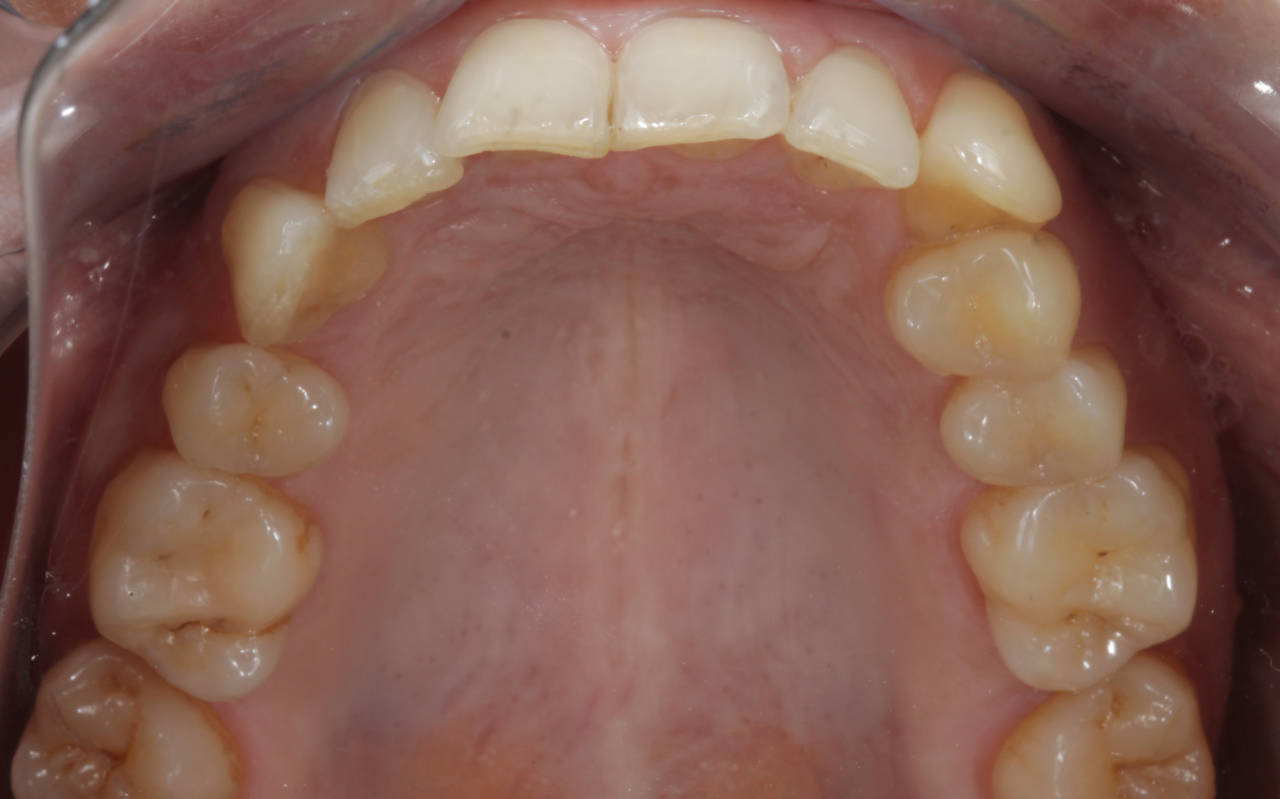

A harmonização do sorriso fez toda a diferença nes